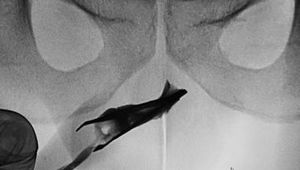

Ngilu! Momen Dokter Temukan Pinset 'Nyangkut' di Mr P Selama 4 Tahun